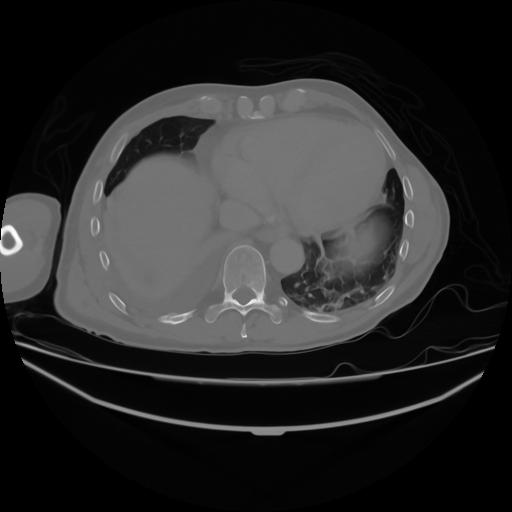

4 CUERPO,CE,Axial,3.0,CUERPO,,